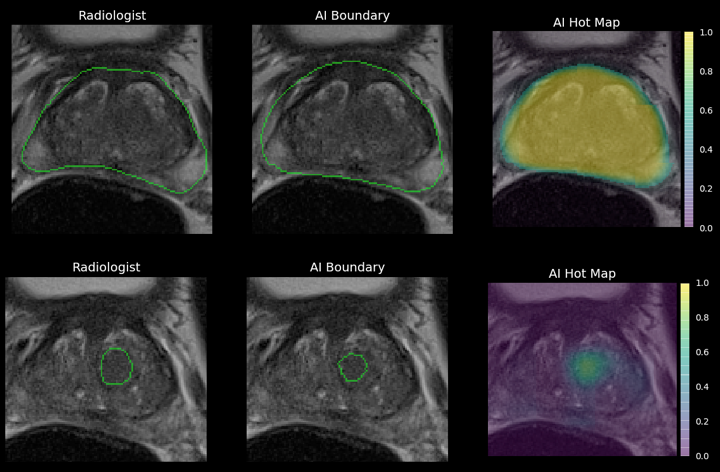

Inicialmente, Ezra llegó al mercado con una única prueba para detectar el cáncer de próstata utilizando el aprendizaje automático para diagnosticar las pantallas que se desprenden de un examen de resonancia magnética abreviado que toma 20 minutos.

Si bien Ezra puede detectar diferentes tipos de cáncer, la tecnología de la empresa no ofrece un diagnóstico. Eso aún depende de un médico y requiere pruebas adicionales. “Estamos convirtiendo las IRM de lo que es una prueba de diagnóstico en una prueba de detección”, dice Gal.